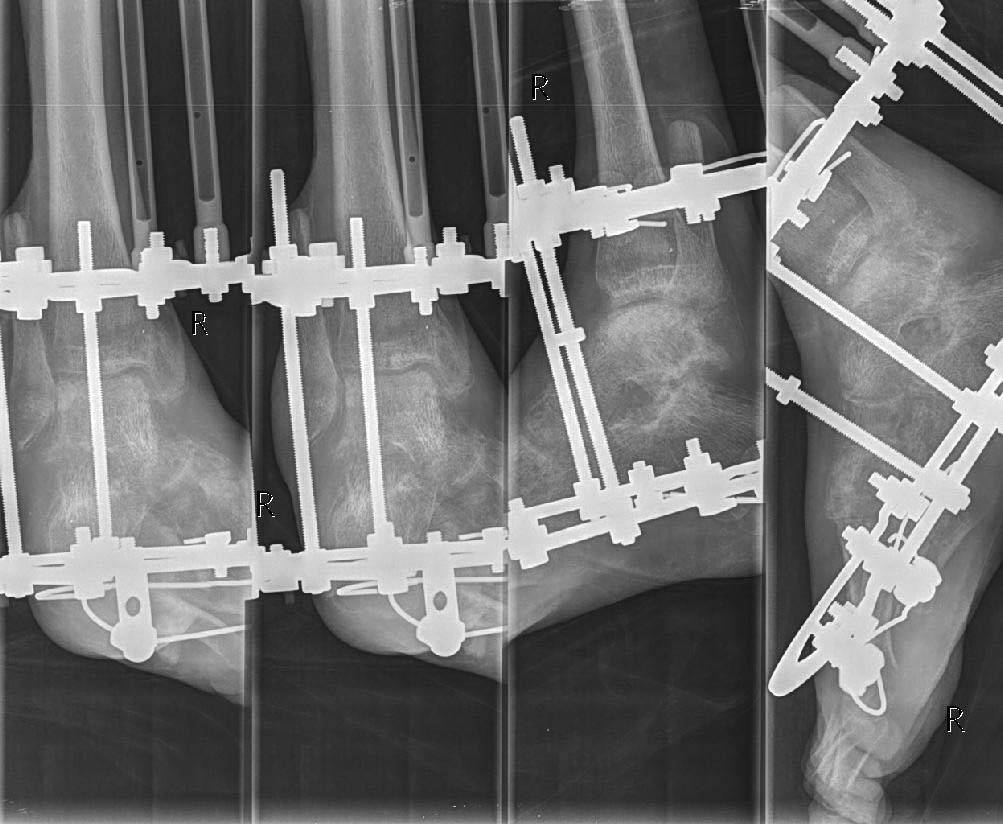

На лечении находится пациент 19 лет, получивший травму в августе 2014года, по поводу чего проходил лечение в ряде ЛУ. В настоящее время имеем правую стопу,вэквино-варусном положении, дефект диафиза малоберцовой кости около 8 см. с дефектом мышцнаружной группы мышц правой голени, кожный покров восстановлен пластически.

Прирентгенографии: подвывих стопы кнутри, выраженный остеопороз. Левая нижняя конечностьэкзартикулирована в тазобедренном суставе. Планируем первым этапом устранить деформациюв аппарате Илизарова, затем выполнить артродез. Здесь возник вопрос: выполнить артродезтолько голеностопного или совместно с подтаранным суставом. Каково Ваше мнение?

Добрый день. Для обсуждения метода лечения желательно на форум представить рентгенографию голени,голеностопного сустава,стопы и фото голени пациента.Если нет дегенеративных изменений в подтаранном суставе, то лучше ограничится артродезом голеностопного сустава.

Добавляю фото и рентгенограммы.

Учитывая выраженные изменения в подтаранном суставе и для восстановления опороспособности конечности целесообразно выполнить панартродез в аппарате.

Уважаемые коллеги! Спасибо за советы! Сегодня выполнен артродез голеностопного сустава винтами, подтаранный сустав решили оставить "на потом".